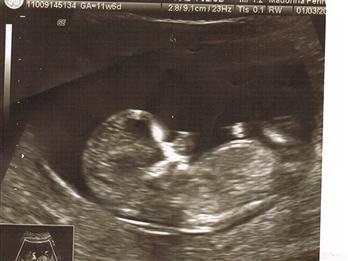

Re: ultrascreen---nub guesses-more pics!

Thanks for yourguesses...I added more pics...hopefulyy they are better!